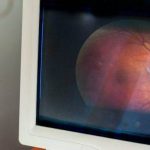

Digital retinal imaging, also known as a retinal photograph, is a non-invasive, diagnostic tool that produces digital high resolution, colored images of your retina, optic nerve, and blood vessels in the back of your eye.

Next, you will open your eyes as wide as possible and stare at an object straight ahead. A bright flash will be seen when the photograph is taken, capturing high definition images of your retina and optic nerve.

The images are displayed on a computer screen for your eye doctor to review with you.